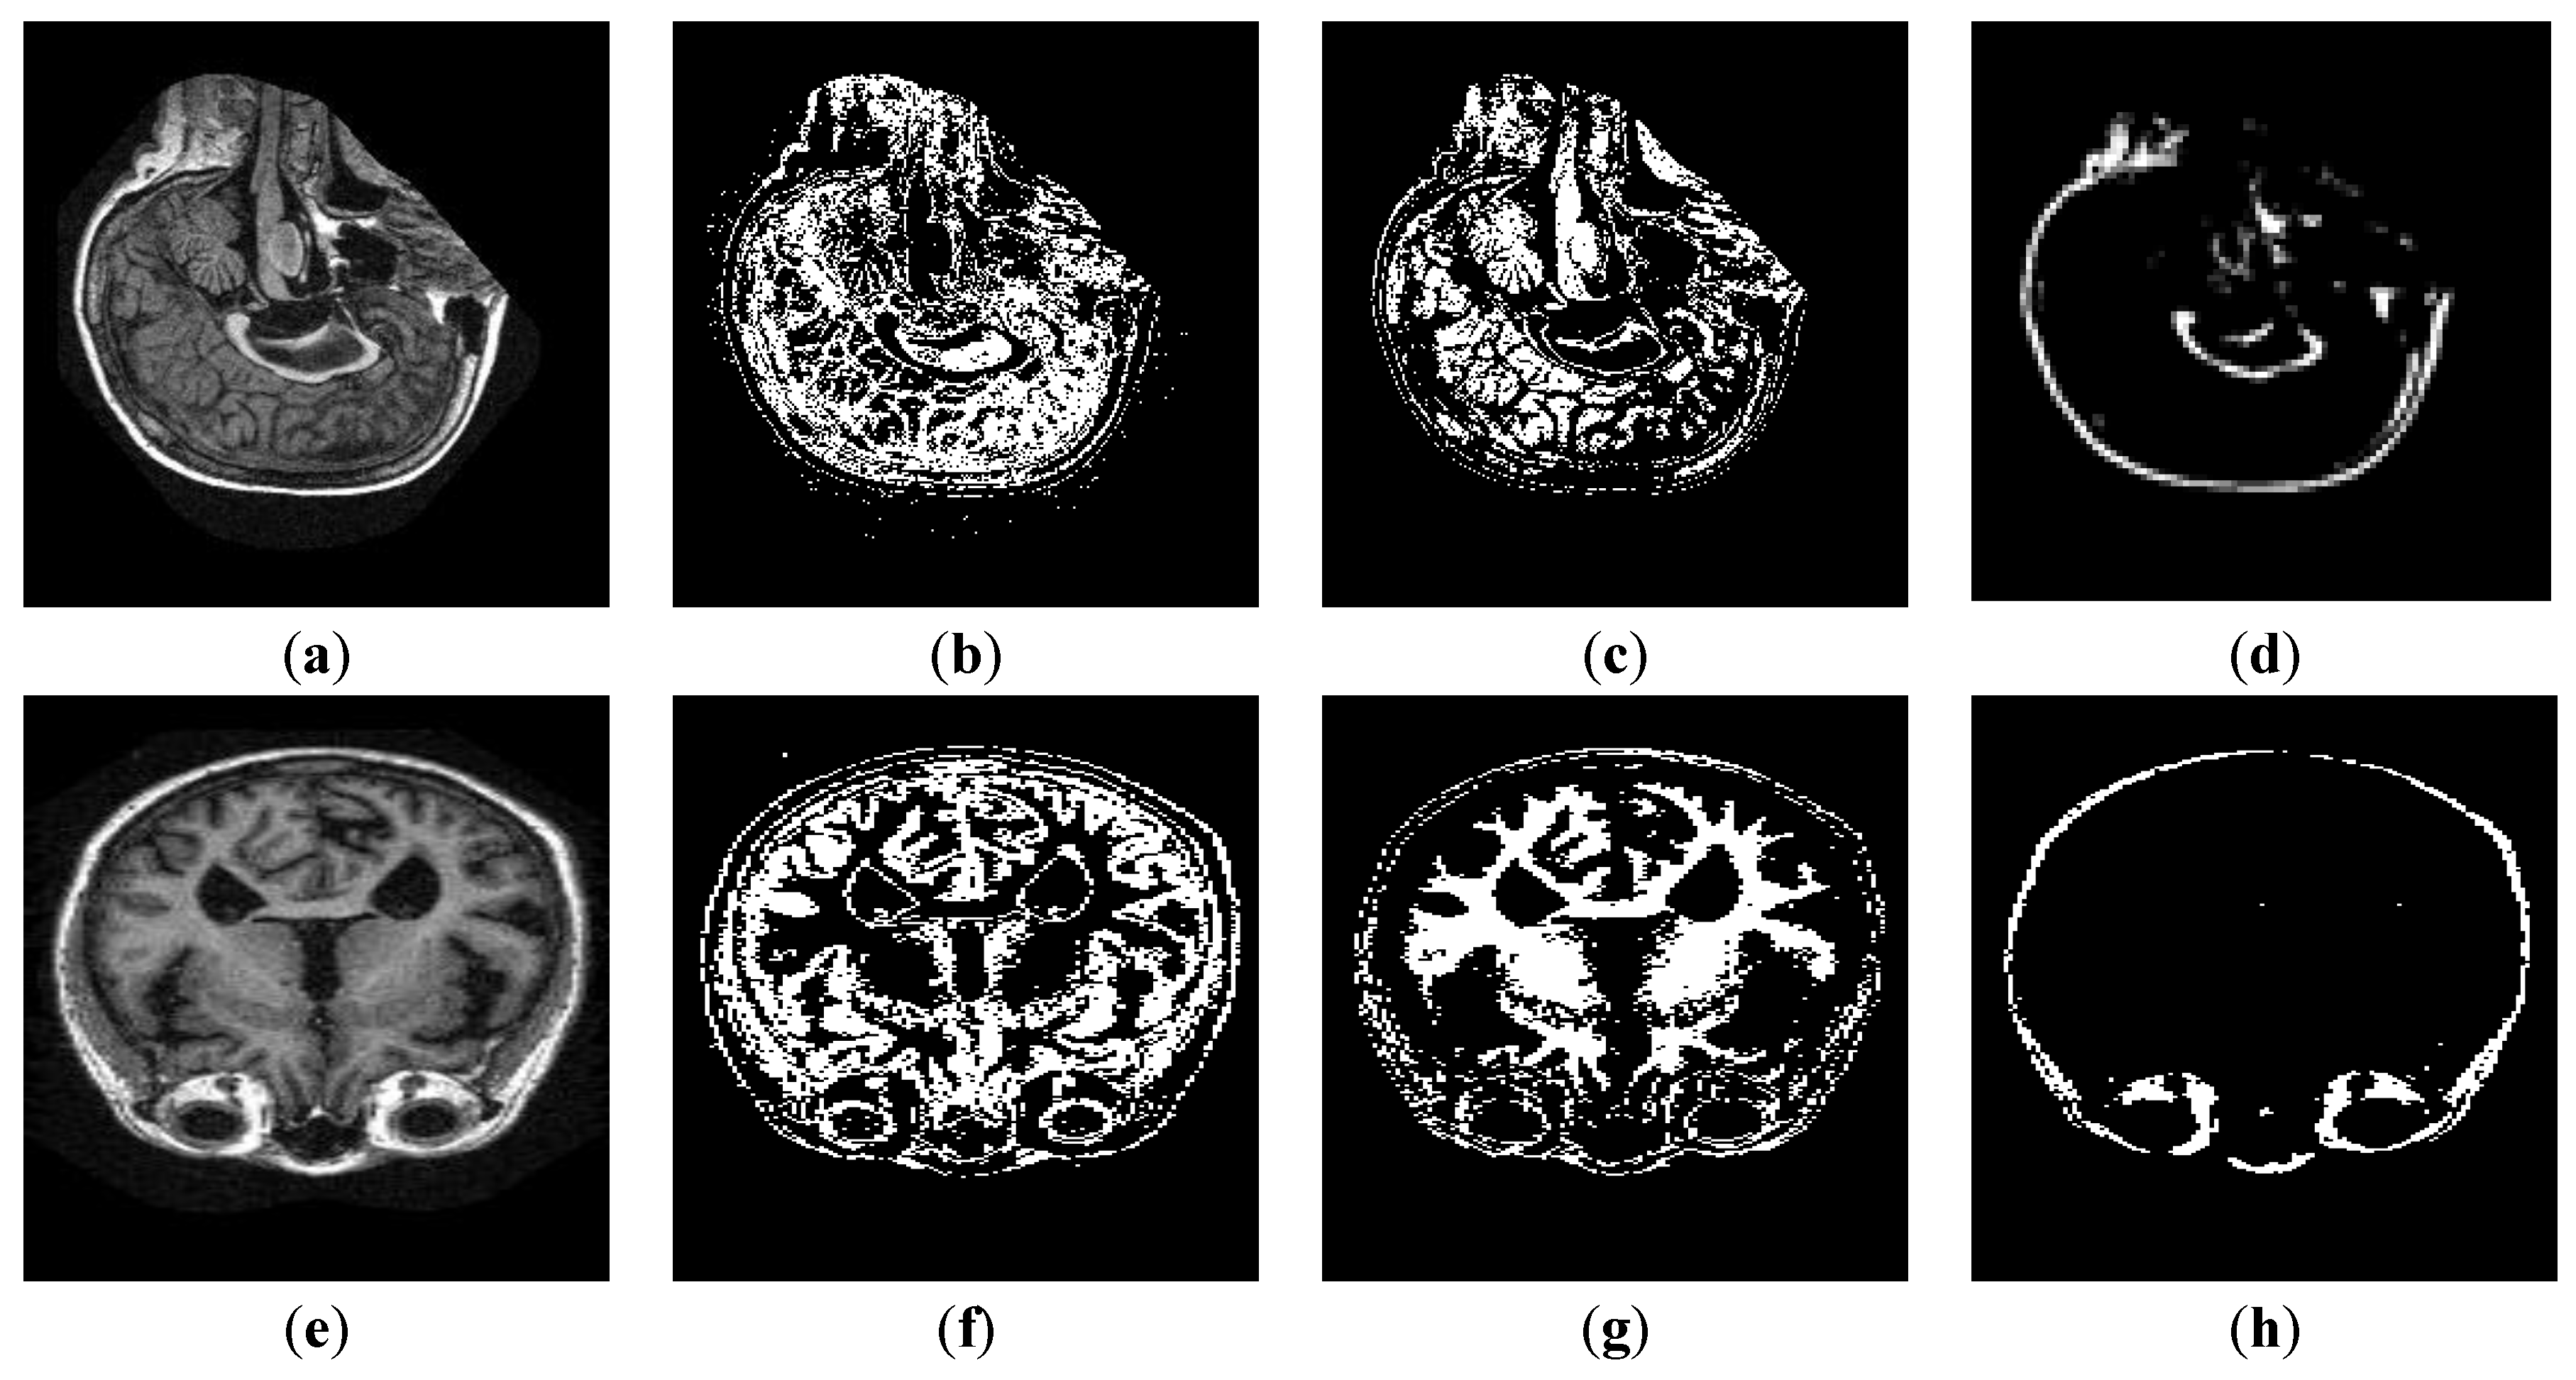

4.6.2. Segmentation Results

4.6.3. Layer-Wise Results of AlexNet